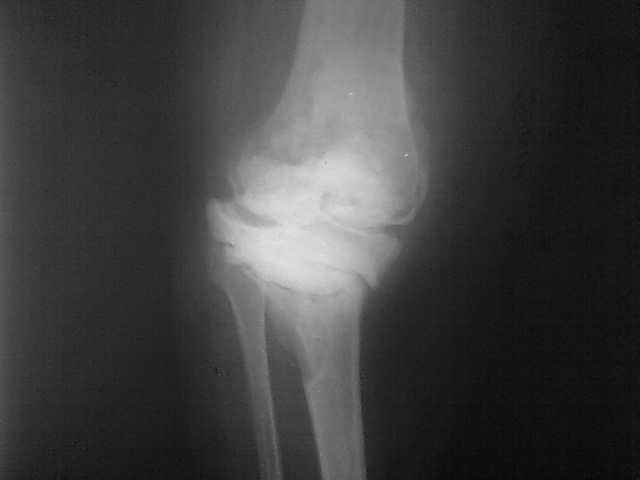

Уважаемые коллеги, прошу Вашего совета по тактике лечения. Женщина 1952 г.р., оперирована в

2006, в одной клинике установлен эндопротез правого коленного сустава, через год

нестабильность обоих компонентов, доктор выполняет ревизию обычным протезом с задним

стабилизатором. В октябре 2008 - нестабильность, свищ. В другом стационаре все удалено,

спейсер с гентамицином, длинный курс антибиотиков.

Коллатеральных связок нет. Собственная связка надколенника цела. До удаления протеза -

выраженная смешанная контрактура. Сейчас свищей нет, анализы в порядке. Планы: Стоит выбор

1) Обычный hinge с цементными ножками, вставками под тибиальным и бедренным компонентами с

импакционной костной пластикой аллокостью с применением сеток для удержания

трансплантата на tibia; 2) Онкологический hinge - с замещением проксимальной голени и

сохранением бедра; 3 - артродез. Заранее благодарен. Римашевский Д.